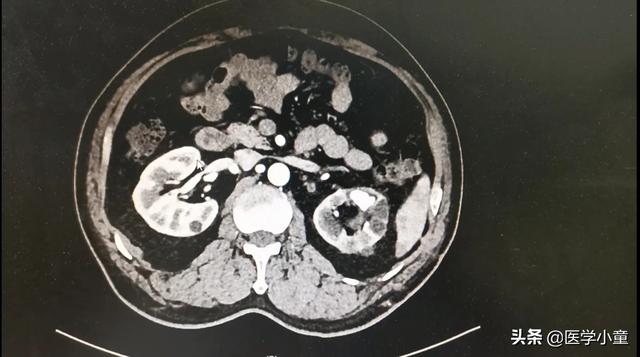

◆ ≥2cm gros calculs, calculs rénaux complexes

Choisissez la néphrolithotomie percutanée mini-invasive, qui ne nécessite qu'un petit trou (de la taille d'une fève de soja) dans la région lombaire, et qui pénètre dans le rein à l'aide d'un néphrolithoscope combiné à un laser holmium allemand pour fragmenter le calcul avant de l'extraire.

Attention :La clé de la néphrolithotomie percutanée réside dans la nécessité de ponctionner les reins du patient, ce qui peut endommager les vaisseaux sanguins rénaux et provoquer des événements dangereux tels que des hémorragies si cela n'est pas fait avec précaution, de sorte que les exigences en matière de spécialistes sont également très élevées.